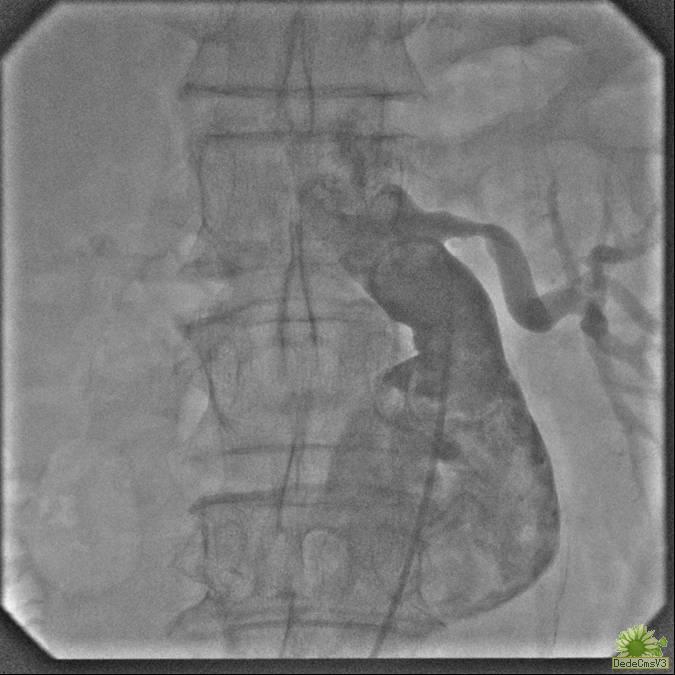

腔内隔绝术治疗腹主动脉瘤

腔内隔绝术(End vascular graft exclusion,EVGE)治疗腹主动脉瘤(Abdominal aortic aneurysms,AAA)与传统手术切除加人工血管移植治疗方法相比,具有创伤轻微、并发症少、病死率低等优点。